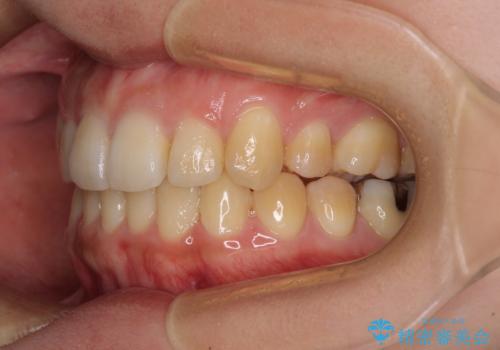

八重歯の抜歯矯正 補助装置を用いたインビザライン矯正

- 下の前歯のデコボコを気にして来院された患者様です。

来院当初、上顎の八重歯は気にしていらっしゃらなかったのですが、矯正治療をするのであれば、しっかりと治した方が良いと説明し、全顎矯正を行うこととしました。

八重歯の移動量が多く、インビザライン単体での治療は困難と判断し、補助装置により八重歯移動後にインビザラインを用いることとしました。